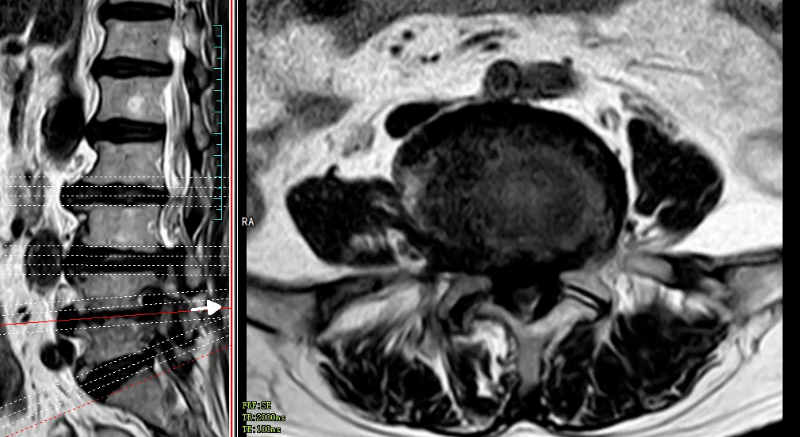

84岁高龄的田婆婆(化名)反复腰腿痛、双下肢麻木、间歇性跛行多年。近半月来病情不断加重,已严重影响生活。于今年的5月份,到我院脊柱外科就诊。经检查,诊断田婆婆腰椎椎管狭窄严重,压迫马尾神经导致马尾综合征,有明确手术指征,但田婆婆已84岁,合并有众多基础病,手术创伤大,风险高,而通过UBE技术进行减压同样可达到减压的目的,且手术创伤小,出血少。

术前MR可见腰3/4、腰4/5椎间盘突出,伴椎管狭窄严重、神经根受压、马尾神经冗余。